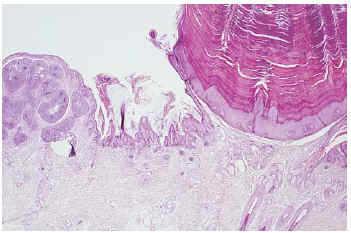

Fig. 4.--Nevo sebáceo asociado a verruga vírica con inducción de la epidermis de tipo basaloide.

En múltiples casos encontramos una inducción de la epidermis de tipo basaloide, de mayor o menor intensidad, constituida por células basaloides pequeñas, a veces con formación de empalizada periférica, que no llegaba a formar tumor.